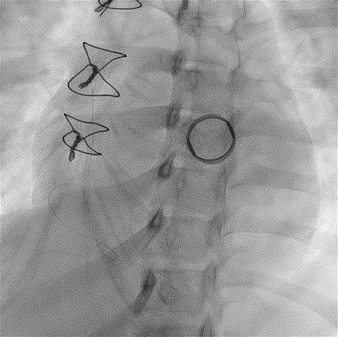

Since TLT was not possible and surgeon refused for emergencyTranscatheter valve disruption was planned. The issues involve in the procedure were 1.Septal Puncture -due to pericardial patch in IAS, alteredanatomy due to Sx & ac dilatation of LA- Angle of puncture and Site ofpuncture. 2 Selection of wire3.Balloon- Size, make ( Compliant Vs NC), 4.Complication-like disc embolization, stuck disc leading to ac severe MA and strud fracture. The septa puncture was done as standard approach, a V18 wirewas parked in PV through a 7f Mullin sheath, Straight Turmo wire was was takenthrough a 6 JR to cross the valve and a 6 x 40 Armada balloon was dilatedacross the disc. Good acute result was obtained. The LA mean decreased from36-40 to 10-12mmHg. Post procedure the inotropic support, O2 demand decreasedover next 12 hr. However after 24 hr pt developed refractory RH failure and persistentanuria requiring SLED. And pt succumbed to the procedure 3 days after theprocedure.